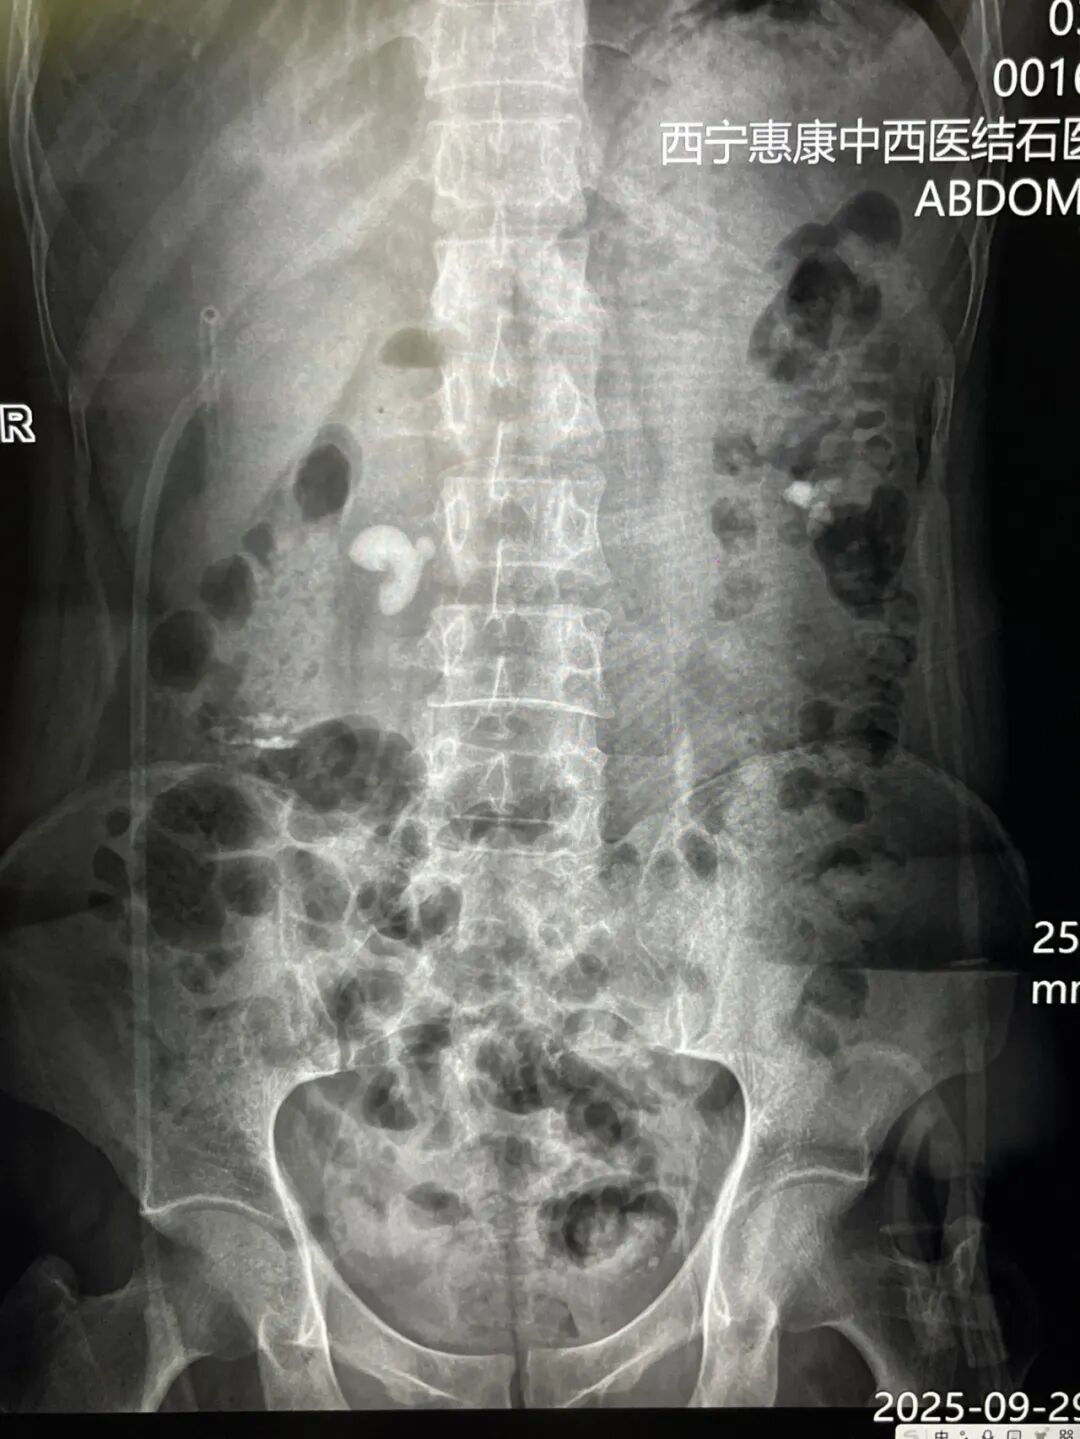

该患者2个月前曾接受左侧输尿管支架管置入术,近期因身体不适前往我院就诊,入院诊断:肾输尿管结石伴有积水和感染(左侧),肾积水伴肾结石(右侧),肾功能不全,入院后组织科内会诊及术前检查,考虑输尿管上段结石,体积大,且与输尿管粘膜黏连严重,俗称“肉包石”,且合并左肾多发结石,综合考虑经皮肾微造瘘碎石取石术。

针对患者的病情,我院泌尿外科立即组织多学科协作团队开展病例讨论。团队结合患者既往手术史、影像学检查结果及身体整体状况,进行多维度评估后认为,需通过联合手术清除结石、改善尿路通畅度并控制感染,最终确定联合手术方案的治疗方案,左肾微创碎石取石及右肾造瘘术。术前,分肾功能测定,右肾仅剩5%;ct片显示,右肾皮质尚有一定厚度,我院医疗团队判定右肾仍有恢复的可能,为尽可能保留右肾参与功能,于是进行了右肾穿刺造瘘。3个月以后进行复查,进行再次的分肾功能测定之后了解右肾功能恢复状况再进行下一步的治疗方案。

对于左肾,我院医疗团队决定保留肾造瘘管引流,有利于其变形的肾盂结构恢复,待左肾引流一段时间之后,从原造瘘口清楚残余结石。手术过程中,诊疗团队严格遵循手术规范,主刀医生凭借多年临床经验与规范操作,在经皮肾镜辅助下逐步击碎并取出左肾及输尿管内的结石,从根源上解决梗阻问题;同时更换原有输尿管支架管,确保术后尿液能够顺利引流,避免再次梗阻;右肾造瘘术的实施则进一步缓解了肾脏压力,为控制感染、保护肾功能提供保障。整个手术历时数小时,各环节衔接有序,最终顺利完成。